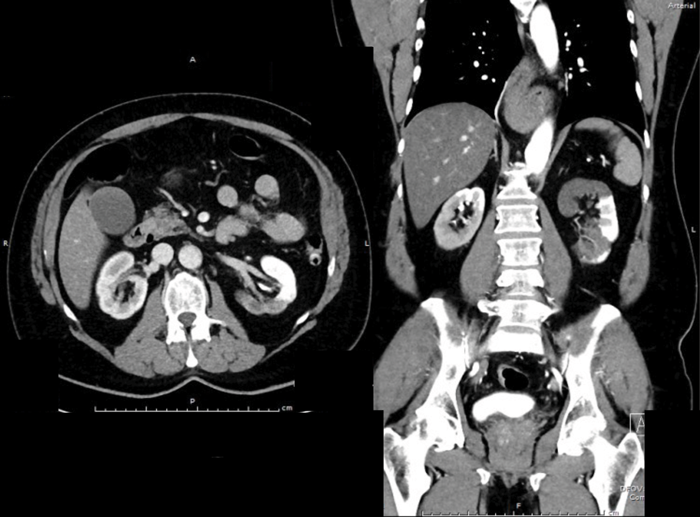

A previously fit and well 65-year-old man presents with acute onset, left loin pain and non-visible haematuria. He underwent a CT KUB suspecting renal stones (no stones seen), therefore he had a subsequent contrast CT scan. These images are shown below:

- What do the contrast CT images show?

There is diffusely marked hypo perfusion throughout the right kidney. The left kidney demonstrates an infarction of the posterior and superior segments of the left kidney.